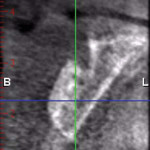

A healthy 27-year-old female oral surgery resident was referred to the author’s private office for implant replacement of missing tooth No. 7. A CBCT revealed inadequate ridge width (3 mm to 3.4 mm) for the placement of a 3.3-mm diameter implant in ideal prosthetic position (Figure 4). Horizontal augmentation was proposed and consent signed. The patient began taking amoxicillin (1.5 g/day) one day prior to the surgical appointment. She rinsed with 0.12% chlorhexidine gluconate for 1 minute just before the procedure. Four 9-ml tubes (Vacuette® blood collection tubes, Intra-Lock International, www.intra-lock.com) of whole blood were collected with a butterfly needle (Vacuette® Butterfly Blood Collection Set, Intra-Lock International). The blood was immediately spun in a dedicated L-PRF centrifuge (IntraSpin®, Intra-Lock International) at 2,700 rpm for 12 minutes. During the blood spin, local anesthesia was administered (xylocaine 2% with epinephrine 1/100,000).

A 65-year-old woman had recently lost a fractured tooth No. 12, which was the anterior abutment for a fixed prosthesis extending to No. 15 (Figure 16). The CBCT cross-sectionals revealed a vertical and horizontal bone deficiency at No. 12, a narrowed ridge at site No. 13, and 2 mm of subantral bone at site No. 14 (Figure 17). The patient was informed she would need vertical and horizontal augmentation as well as sinus elevation prior to implant placement at site Nos. 12, 13, and 14.